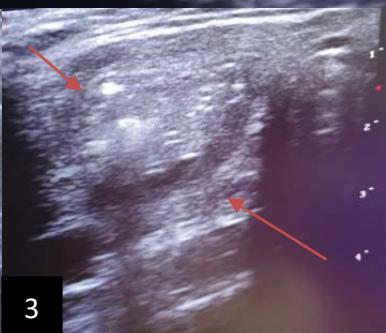

Iconography B: Patient with a 108 ml right isthmo-lobar thyroid hematocele during the first drinking session. A. Materials used before sclerotherapy, B. Image showing a right anterior and lower cervical swelling, Ultra sonographic image: showing a hypoechoic mass dotted around the partitions of 108 ml, D. image showing after ultrasound-guided puncture showing hematic content in the syringe, E. Ultra sonographic image in B mode, showing linear hyper echogenicity of the needle.